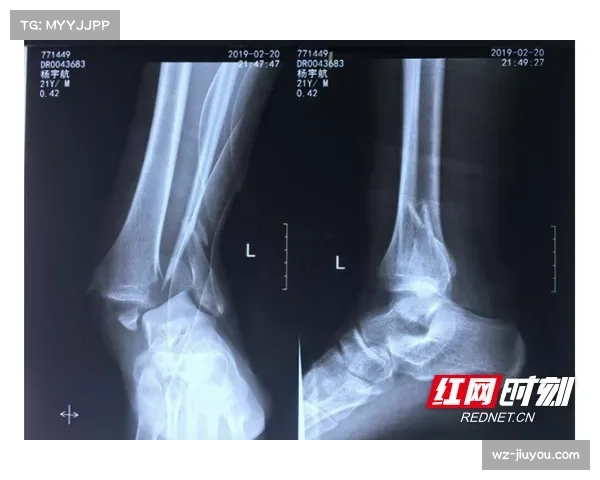

科利尔的左脚踝在比赛中的一次意外动作导致受伤,当时情况令人揪心。运动员脚踝的伤情往往容易涉及韧带、关节以及骨骼,一旦出现骨折,恢复周期极长,甚至可能对职业生涯造成巨大影响。因此,初步检查的结果显示未发生骨折,可以说是最令人欣慰的消息。这意味着科利尔很可能只需要通过休养与康复训练来恢复,而不必接受复杂的手术与长时间的固定治疗。

在医学角度来看,骨折与软组织损伤的区别极为重要。骨折需要较长的固定期,而软组织损伤虽然也会影响运动表现,但恢复周期相对较短,且康复方式更多样化。通过初步影像学检查和临床评估,医生能够快速确认是否存在骨折,从而制定合适的康复计划。科利尔的检查结果显示未见骨裂,这为其尽快回归赛场奠定了良好基础。